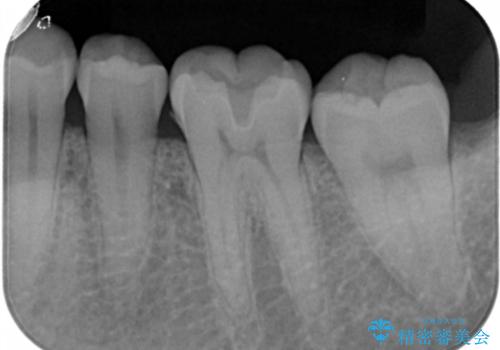

- 左下6番の治療のやり直しを希望し来院された患者様です。

保険の材料が劣化し段差や隙間ができてしまっている状態です。

自費の治療を希望されたため切削量・形態を考慮し、セラミックインレーでの治療を計画しました。